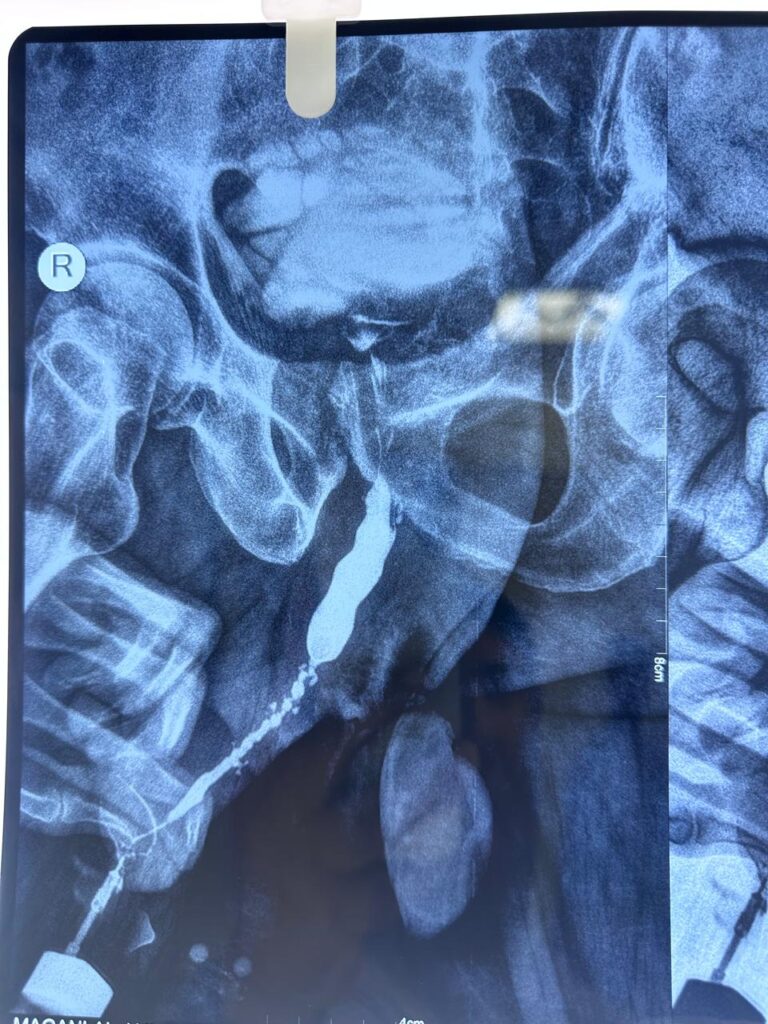

x-ray image

• Retrograde Urethrogram (RGU) – X-ray imaging of the urethra